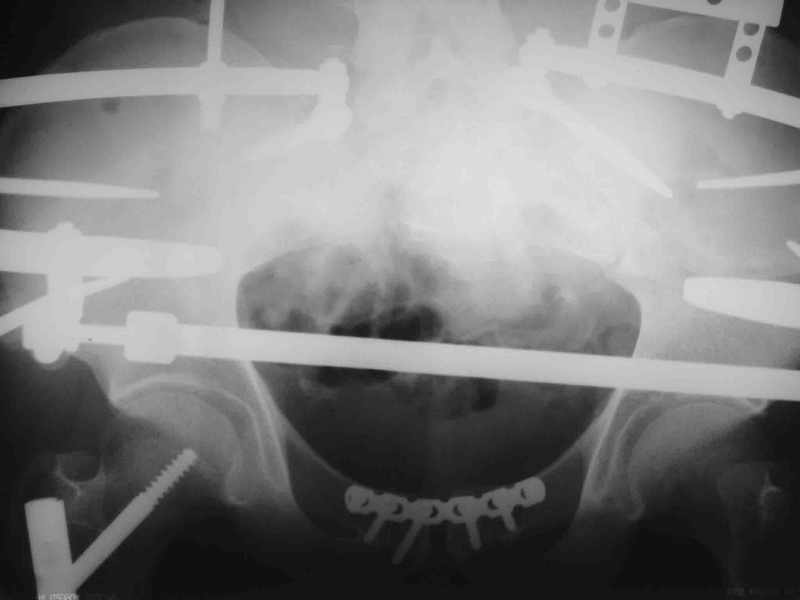

Вот вариант решения похожей ситуации

Алексей Смирнов,

Нижний Новгород